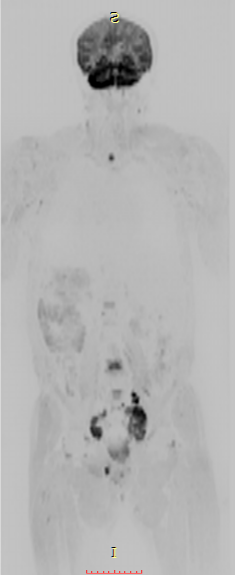

七、全身类PET成像,此项检查技术主要用于全身转移肿瘤的筛查:

①磁共振类 PET成像对全身恶性肿瘤病变性质的诊断,尤其对全身转移灶的筛查,淋巴结转移筛查及恶性肿瘤的分期评估具有很高的价值。②对已明确发现转移性病灶寻找其原发灶;术后放化疗的效应观察等具有较大优势。③对高危人群的肿瘤筛查具有实用价值。